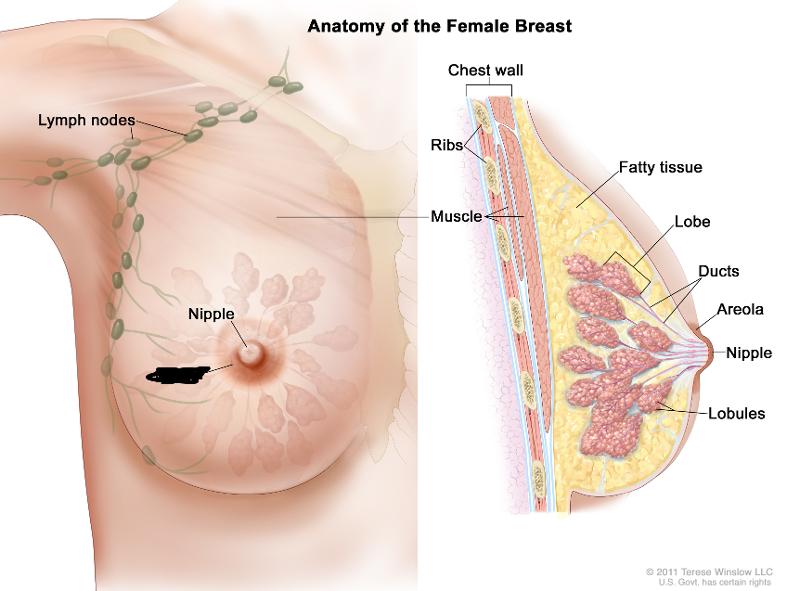

Areola

Lactiferous duct

Mammary glands